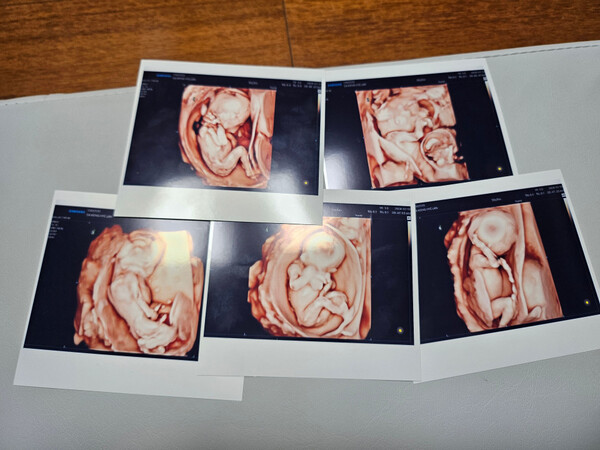

임신 준비 과정에서 알게 된 아내 사공혜란 씨의 다낭성 난소증후군 치료를 시작할 때만 해도 김 씨는 가족계획엔 아이 한두 명뿐이었다. 정확한 배란을 유도하는 첫 치료 후 바로 자연임신에 성공했다. 다행히 빨리 찾아온 아가에게 ‘팡팡이’라는 태명을 지었지만 곧 쌍둥이로 확인됐다. 그것도 둘이나 셋이 아닌 다섯쌍둥이라는 얘기에 걱정이 먼저 앞섰다.

실제로 아내 사공 씨가 아이들을 품는 과정부터 쉽지 않았다. 체구가 작은 편인데 배가 불러오는 속도가 너무 빨라 몸을 가누기조차 쉽지 않았다. 다섯쌍둥이 분만을 담당했던 가톨릭대학교 서울성모병원 측은 "체구가 작은 산모는 출산 예정일인 12월이 되기 훨씬 전부터 만삭처럼 배가 불렀다"라며 "임신과 합병된 고혈압성 질환인 전자간증(임신중독증) 진단으로 출산을 더 미룰 수 없어서 27주에 수술을 결정하게 됐다"라고 밝혔다.

개원 후 처음 있는 오둥이 분만을 위해 산부인과는 물론 마취통증의학과, 소아청소년과 김세연 교수, 분만실 전담간호사 등 다학제 의료진이 사전 계획을 철저히 세웠다. 첫째부터 다섯째까지 적혀 있는 신생아 발찌, 신생아 기록지, 인큐베이터 모두 각각 5개씩 준비했다. 20일 오전 11시 37분 첫 번째 남자아이가 나오고 순차적으로 수술이 이어졌다. 다섯 번째 아가까지 수술실 내 처치를 마치자마자 안전하게 집중치료실로 옮겼다. 남자아이 3명과 여자아이 2명이었다.